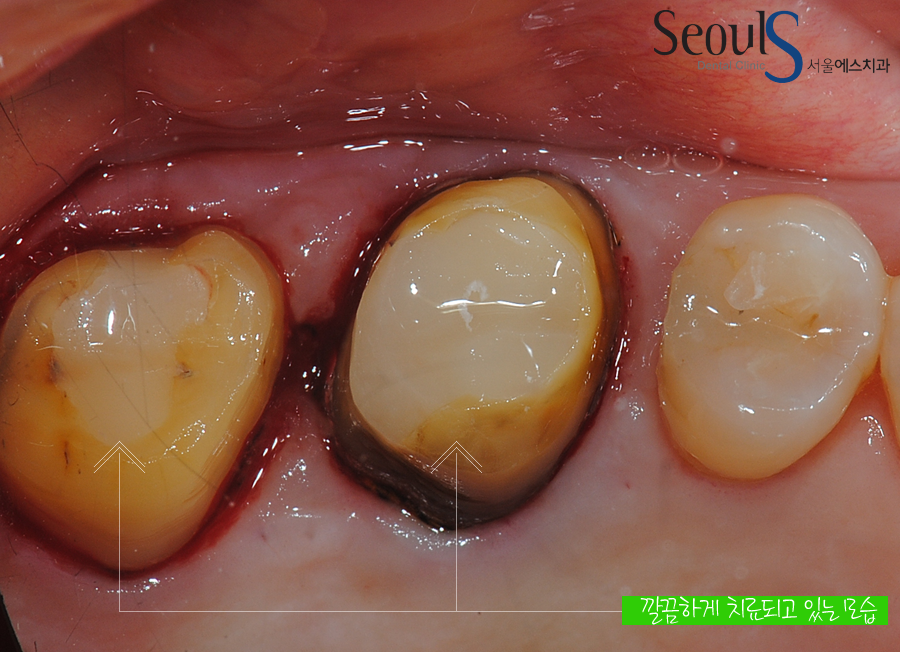

치아를 다듬고 있습니다

깔끔하게 치료가 진행되고 있는 모습입니다